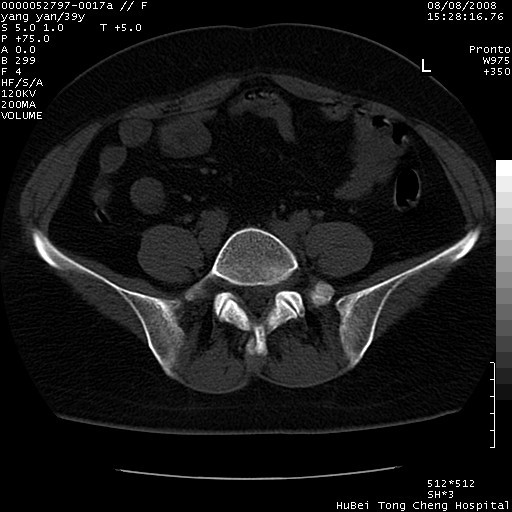

患者 女,39岁。因外伤检查,偶然发现。

典型!双侧骶髂关节致密性骨炎。

典型!病变主要累及双侧髂骨。常见于育龄期妇女。

致密性骨炎,一般不跨越关节面,可是这个骶骨关节面也有硬化。

髂骨致密性骨炎系一种以骨质硬化为特点的非特异性炎症,有高度致密的骨硬化现象,尤其以髂骨下2/3更为明显,但关节间隙则无改变。因位于骶髂关节,且该关节症状明显,故又称之为“骶髂关节致密性骨炎”。 本病90%以上为中年女性,以妊娠后期、尤其分娩后为多见,亦可见于尿路或女性附件慢性感染后,或盆腔内其他感染。此外,臀骶部的外伤亦可诱发或引起本病。  妊娠、分娩及外伤均可引起骶髂关节韧带的撕裂而易使局部的血供受阻。因此早期局部呈现充血、水肿及渗出增加等,渐而局部出现增生与变性反应,随着胶原纤维的致密化而向硬化演变;血管形成厚壁血管,易闭塞而引起髂骨耳状面处缺血和缺氧,骨质呈现硬化性改变,以致手术时局部出血较少。骶髂关节囊壁显示纤维增生、弹性降低及松动样改变。继发于盆腔内炎症者亦出现相类似的病理改变,可能系细菌内毒素作用所致。